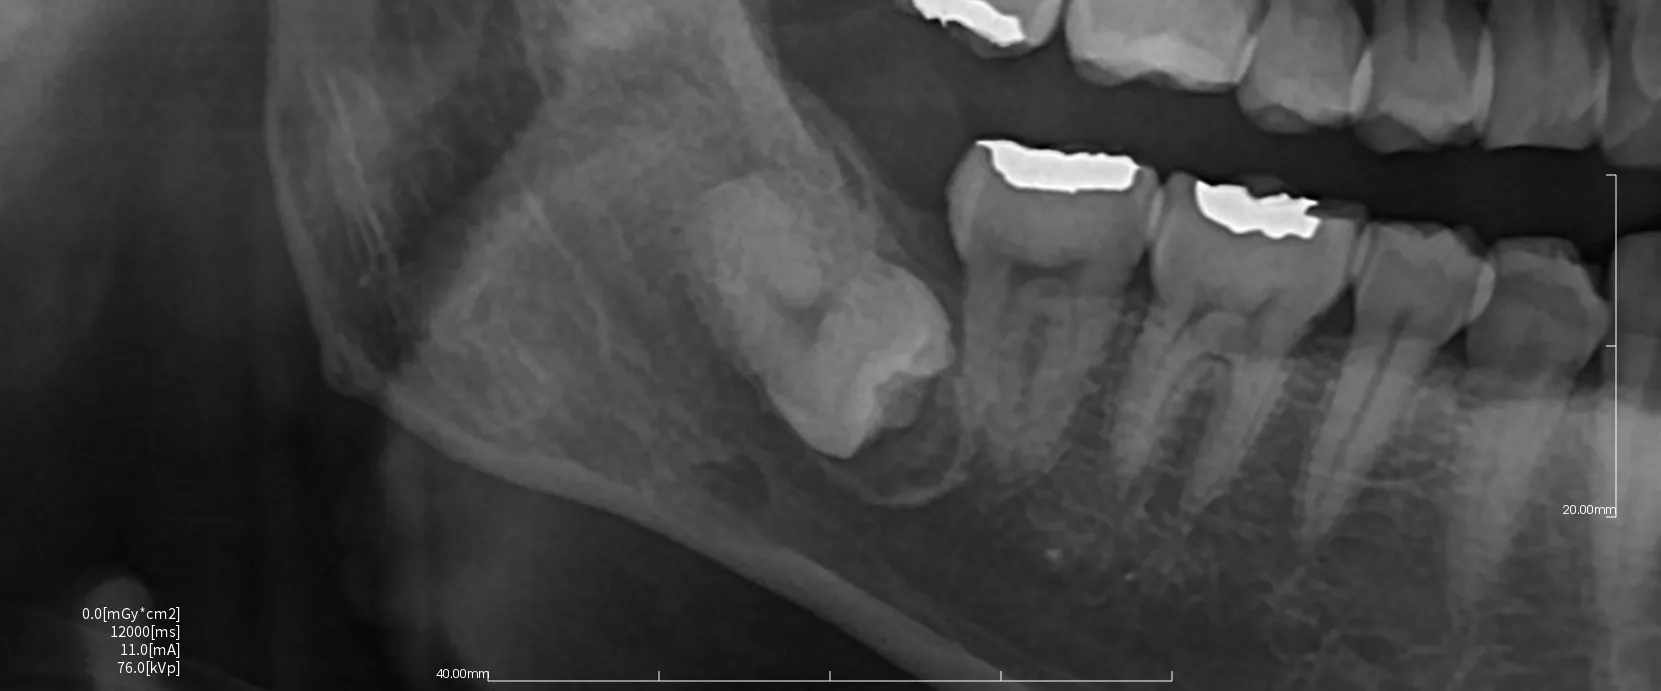

まず親知らずのレントゲン写真を2つお見せします。

どちらも横向きに生えた親知らずですが、抜歯の難易度は大きく異なります。

難易度ではレントゲン写真1>レントゲン写真2となります。

・横向きであることは同じですが、角度は大きく違います。

写真1は下に向かっている。写真2は上に向かっている。

抜歯は口腔内から治療を行うために、上に向いている方が器具が届きやすく、目で見える範囲で治療を行うことができます。

・骨に埋まっている範囲は写真1>写真2。

骨に埋まっている範囲が大きければ大きいほど骨を切削して掘り出す必要が出てきます。

周りの骨を削合すれは当然創傷は大きくなり、腫れや出血、痛みなどの症状も出やすくなります。

・下顎管(神経や血管のある管)との距離や歯の接している範囲

下顎管の損傷は神経麻痺のリスクや大量出血のリスクが大きくともなってきます。

近ければ近いほど、範囲が多ければ多いほど慎重に治療を行う必要があるために抜歯時間も長くなる傾向にあります。

・歯根の開き方

歯根は写真1は単根と言って1つにまとまっています。しかし写真2では2根にはっきりと分かれていてカニの爪のように彎曲もしています。

この場合は写真2の方が難易度は上がってきます。